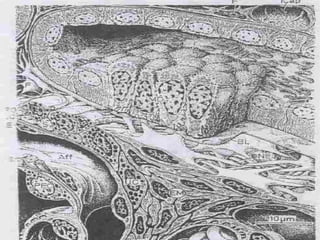

Proksimal Kıvrıntılı Tübül

 Mikrovillusların oluşturduğu iyi gelişmiş fırçamsı kenarlı

bir üst bölge

 Yoğun hücre zarı kıvrımları ve interdijitasyonları içeren

bir bazolateral bölge

 İyonların mağnezyuma bağımlı Na – K pompasıyla

taşınması için ATP sağlayan ve hücre kıvrımları arasına

yerleşik olan uzun mitokondriyonlar

 Endositoz ve küçük proteinlerin amino asitlere yıkımı için

gereken apikal tübüloveziküller ve lizozomlar bulunur.

PKT ve DKT’lerin TANINMASI

Her ikisi de böbrek cisimciğine bitişiktir.

PKT’ler çok fazla miktarda lizozom içerirler

(koyu).

PKT’lerin apikal yüzlerinde belirgin fırçamsı

kenar ve veziküller bulunur.DKT’lerin apikal

yüzlerinde seyrek mikrovilluslar ve vezikül

bulunur.

PKT ve DKT’leri döşeyen hücrelerde bazal

yerleşimli çok sayıda mitokondriyonlar bulunur.